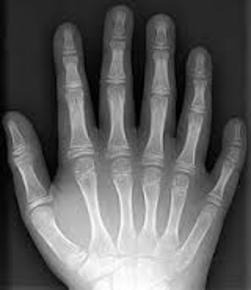

SINDACTILIA: Es la fusión de dos o más dedos de las manos o de los pies; generalmente implica la conexión cutánea entre las dos áreas, pero en casos muy poco frecuentes implica la de los huesos. |

Image:

Sindactilia.JPG (image/JPG)